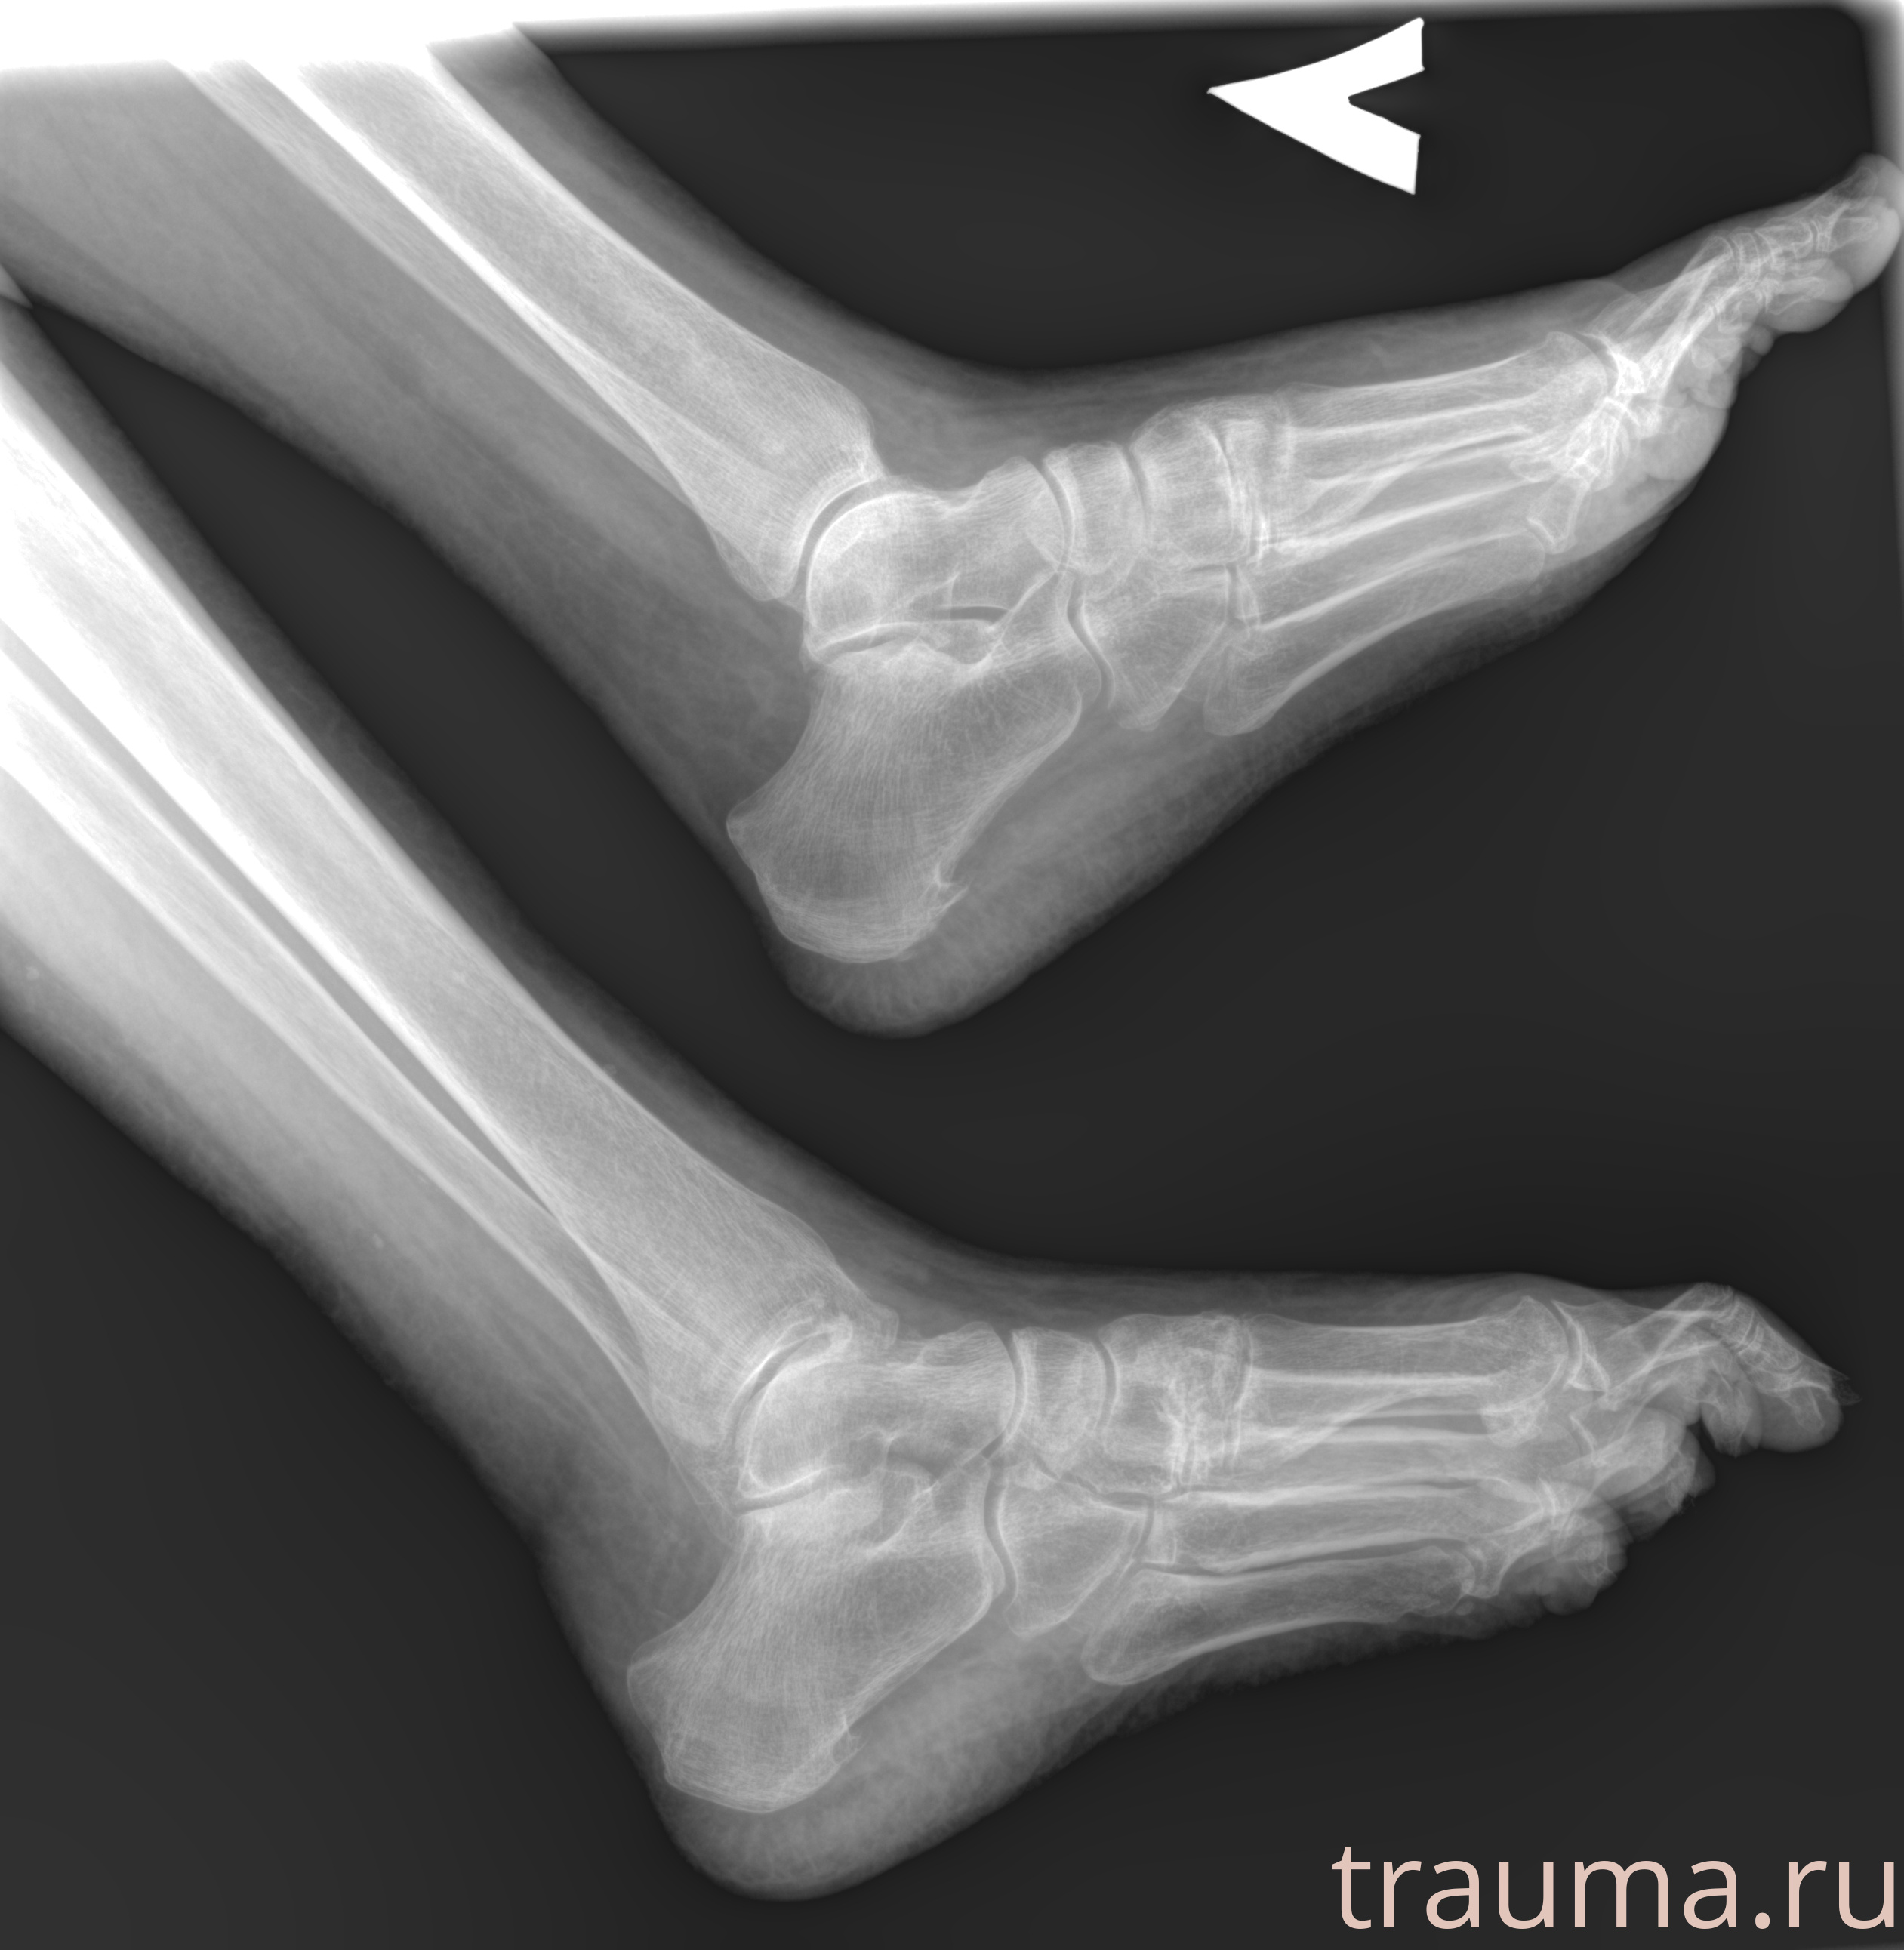

Рентгенограммы

Рентген на дому: по вашему адресу приезжает врач-рентгенолог, травматолог-ортопед с мобильным рентгеновским аппаратом, проводит диагностику травмы или заболевания, делает необходимые рентгенограммы, дает рекомендации по дальнейшему лечению. Получить качественные снимки в домашних условиях возможно благодаря уникальной методике, разработанной МосРентген Центром для института  Склифосовского